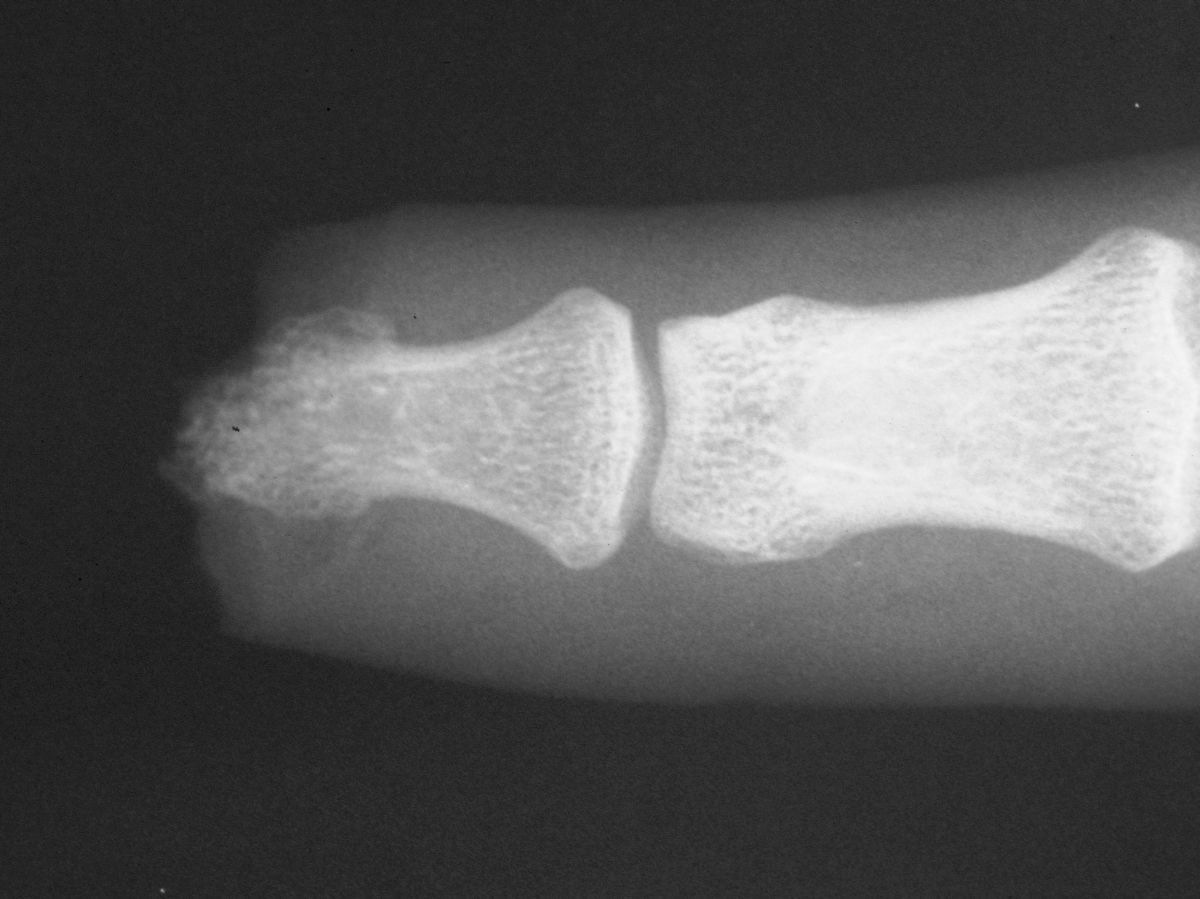

| Case

4. A dog bit off this young man's index fingertip. Although the PA Xray looks as though the bone was kept, additional views show an amputation through the tuft. |